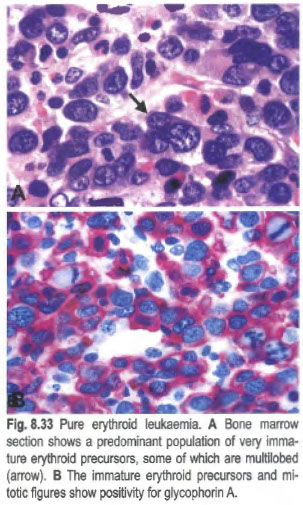

• Pure erythroid leukemia

- erythroblasts in "pure erythroleukemia"